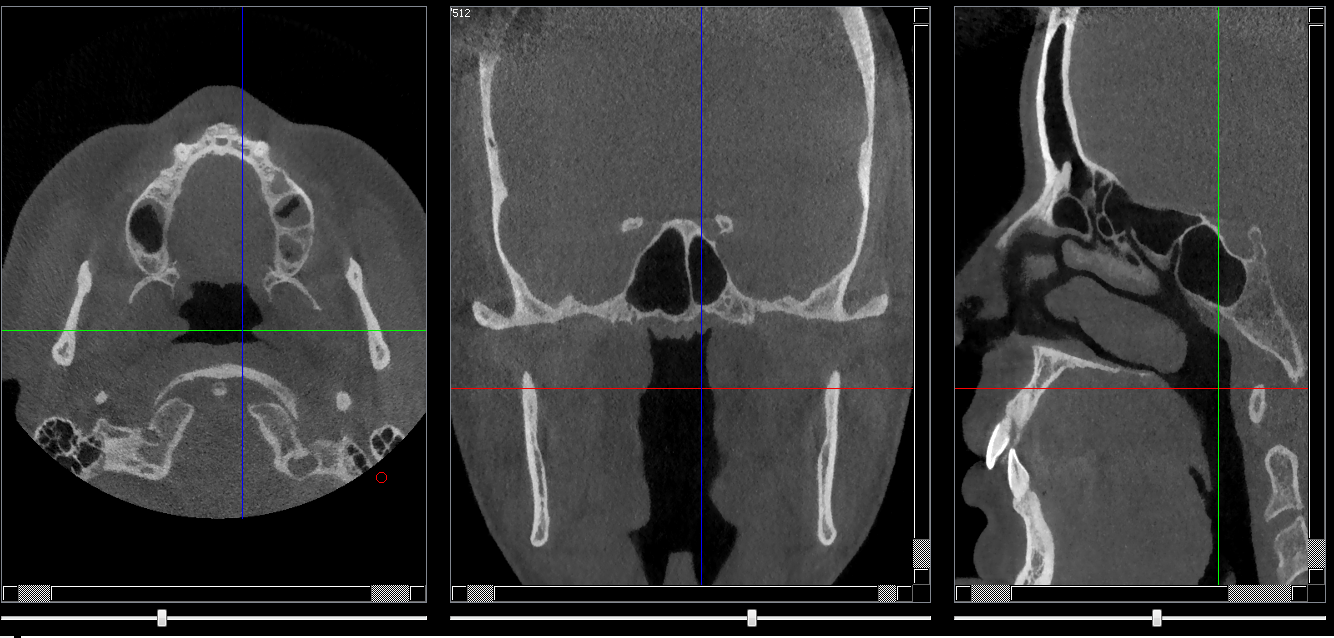

Structures osseuses

Repères anatomiques

- Coupe transversale

- Début : Rhinopharynx

- Fin : clivus

- Coupe frontale

- Début : Partie post du palais dur

- Coupe saggitale

- Début : Processus clinoide droit

- Fin : Processus clinoide gauche